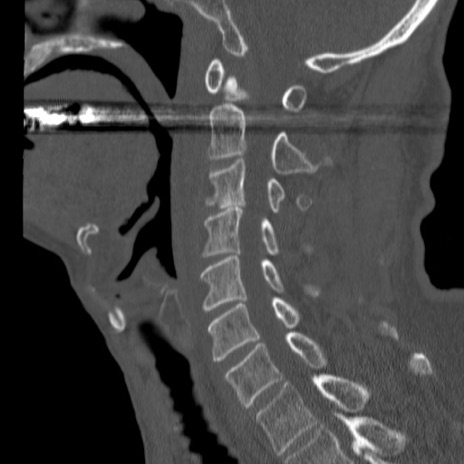

症例46 頚椎CT(矢状断像)

【症例】80歳代男性

【主訴】両側頚部〜上肢のしびれ

【現病歴】昨日、自宅内で転倒、その後より上記症状あり。意識障害なし。

【身体所見】両側上肢のallodynia(熱痛覚過敏)あり。MMTおよびDTRは正確な所見取れず。両上肢の挙上はなんとか可能。

異常所見と診断は?